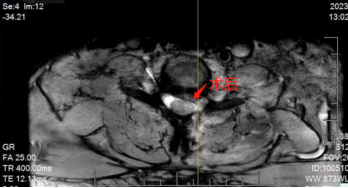

患者术前与术后的颈椎情况对比